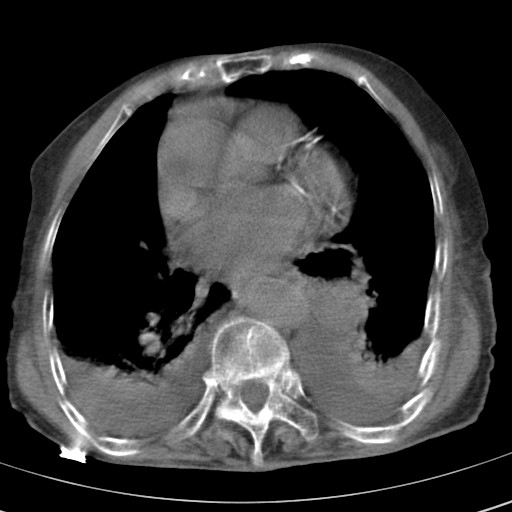

女,93岁,摔伤后检查。

右肺炎症,心功能不全伴双侧胸腔积液,右下肺膨胀不全,食管裂孔疝,冠脉钙化,心包少量积液,左侧肋骨骨折,请上传骨窗.

右侧锁骨\\肩胛骨骨折、右侧湿肺,心功能不全伴双侧胸腔积液,右下肺膨胀不全,左膈破裂或食管裂孔疝,冠脉钙化,心包少量积液,请上传骨窗.

右肺炎症,心功能不全伴双侧胸腔积液,右下肺膨胀不全,食管裂孔疝,冠脉钙化,心包少量积液,左侧肋骨骨折,右肩甲骨粉碎性骨折。93岁,高寿哇!

右肺炎症,心功能不全伴双侧胸腔积液,右下肺膨胀不全,食管裂孔疝,冠脉钙化,心包少量积液,左侧肋骨骨折,右肩甲骨粉碎性骨折。